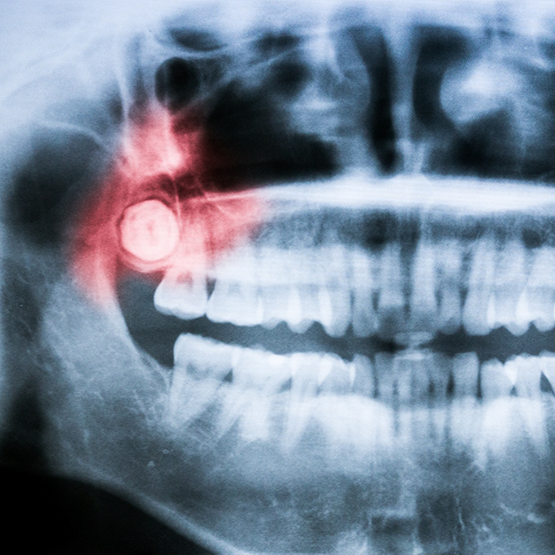

Wisdom teeth are the last molars that grow into the mouth, typically between the ages of 15 and 24. If your child hasn’t had their wisdom teeth assessed to determine whether they need to be removed, Dr. Gaddam and our team at The Dental People can help. Call us today to schedule you or your child’s appointment so we can take care of the wisdom teeth before they cause serious issues down the line.

The Wisdom Tooth Process

If your wisdom teeth have erupted through the gum line and are visible, Dr. Gaddam can likely remove them in-house. Using an instrument called an elevator, she’ll gently lift the wisdom teeth from their socket. Then, our team will remove them from the mouth with a pair of dental forceps and wiggle them free of any connective tissues. Before you leave, we’ll provide you with aftercare instructions to prevent complications like dry socket from occurring.